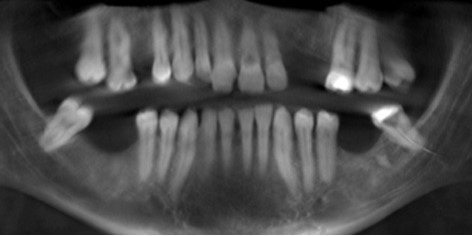

The patient reported that 1 week earlier he had endodontic treatment initiated by a general dentist in his left mandibular third-molar. Two days after the beginning of root canal treatment he developed severe pain and paraesthesia in the left lower lip and chin. On reporting this, a panoramic radiograph had been taken by the referring dentist. It showed a broken endodontic instrument located in the apices of the left mandibular third-molar with an extension toward the IAN (Figure 1). Amoxicillin 1g every 12 hours and paracetamol 500 mg every 12 hours was prescribed by his dentist. The prescribed analgesic reduced pain but paraesthesia in the left lower lip and chin continued and prompted referral by his dentist.

Figure 1.Panoramic radiograph of broken instrument located in the apices with an extension toward mandibular canal.